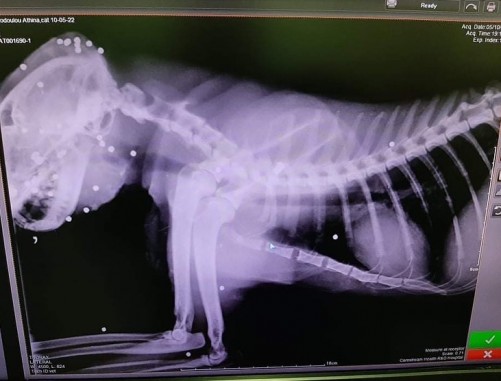

“Πείτε μου τι θα πω εγώ τώρα στον μικρό όταν πάμε στην Λεμεσό, στον παππού και στην γιαγιά και δει το αγαπημένο του γάτο σε αυτή την κατάσταση; Αν καταφέρει να βγει νικητής ζωής ο κακόμοιρος αφού κάποιοι «κακοί άνθρωποι» αποφάσισαν να τον κάνουν σκοποβολή με τα φλομπέρ την Κυριακή. Τα κατάφερε όμως ρε, και δεν τον σκοτώσατε έτσι για να ξέρετε! Ο «Δίας» είχε την δύναμη και την θέληση για ΖΩΗ και επέστρεψε σπίτι του και ήδη νοσηλεύεται σε κλινική! Και θα τα καταφέρει γιατί έχει κάτι που εσείς δεν έχετε ούτε θα έχετε ποτέ! Έχει καρδιά, και αγάπη μέσα του όχι μίσος και κακία σαν εσάς”, σημειωνόταν στην επίμαχη ανάρτηση, σύμφωνα με την ιστοσελίδα sigmalive.com

Δείτε φωτογραφίες από την κακοποίηση γάτας στην Λεμεσό. Προσοχή σκληρές εικόνες